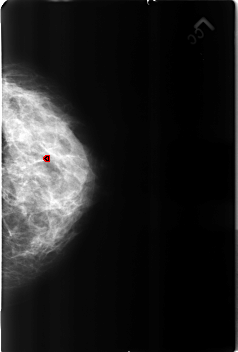

B_3162_1.LEFT_CC

FILE: B_3162_1.LEFT_CC.OVERLAY

TOTAL_ABNORMALITIES 1

ABNORMALITY 1

LESION_TYPE CALCIFICATION TYPE LUCENT_CENTERED DISTRIBUTION N/A

ASSESSMENT 2

SUBTLETY 4

PATHOLOGY BENIGN

TOTAL_OUTLINES 1

BOUNDARY